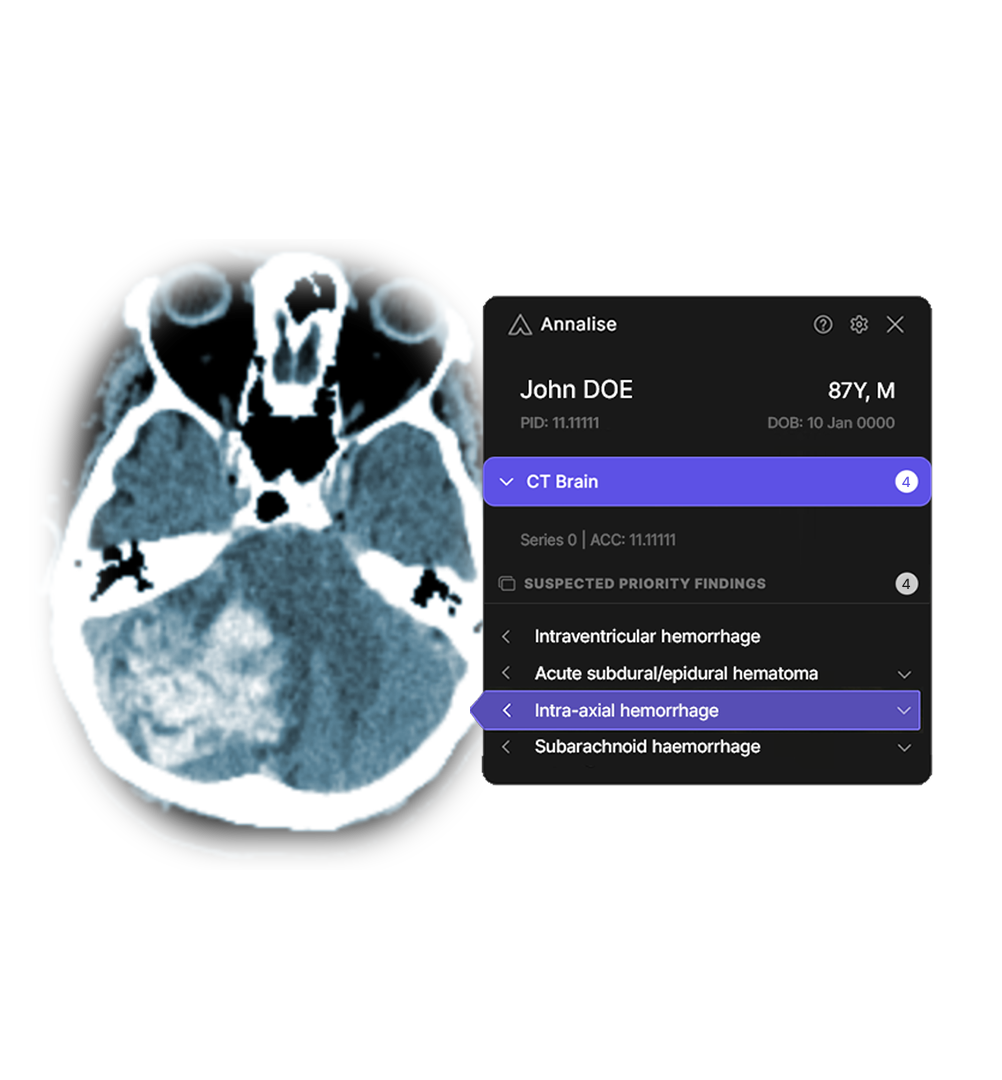

This strategic relationship includes plans to implement Annalise.ai’s comprehensive radiology AI product, called Annalise Triage, across the Mass General Brigham system, according to a written statement issued about the collaboration by Annalise AI. The collaboration will be executed through Mass General Brigham’s newly launched AI business office that supports the development of AI-enabled software as medical device products from concept, to prototype, to validation, to clinical adoption.

Annalise.ai is a global medical imaging AI company, with regulatory clearance for clinical use in over 40 countries including the US. Annalise Triage, an FDA-cleared worklist triage solution that is set to be deployed across the Mass General Brigham system, can automatically and rapidly monitor all chest X-ray (CXR) and non-contrast head CT (NCCTB) exams for time-sensitive critical findings and alert clinicians. Annalise Triage has the most FDA-cleared findings for both of these modalities, and Annalise has also earned breakthrough designation for obstructive hydrocephalus.